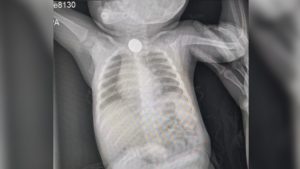

Монета на обзорной рентгенографии ребенка

Обычно уже в условиях стационара малышу назначаются такие процедуры, как рентген или эндоскопия ЖКТ, все зависит от результатов предварительного осмотра и возраста пациента. Исследования подобного рода помогут максимально быстро определить, в каком именно месте расположена проглоченная монета.

Доктор также поможет определить точное положение монеты в вашем ребенке с помощью рентгена, и вы можете быть уверены, что объект, который проглотил ваш ребенок, — это просто монетка и ничего больше.

- Рентген. Позволяет обнаружить местонахождение монеты;

В отличие от пластмассовых деталей монету легко отследить на рентгене.

Для правильного выбора тактики лечения важно выяснить, где именно она находится, поэтому родителям нужно либо вызвать скорую помощь, либо самостоятельно отправиться в приемное хирургическое отделение детской больницы (с проглоченными металлическими предметами нужно обращаться именно в хирургию, а не в отоларингологию) для проведения необходимых мероприятий.

Ориентироваться только на эти признаки нельзя, потому что поведение некоторых детей не меняется вовсе. Точное местоположение монеты можно увидеть только на рентгене.